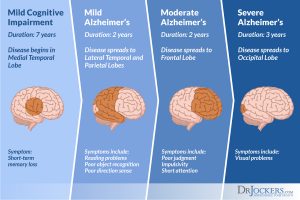

Embrace seasonal changes with our predicting alzheimers disease progression using a versatile sequence gallery of countless weather-themed images. highlighting time-sensitive blue, green, and yellow. perfect for seasonal marketing and campaigns. Each predicting alzheimers disease progression using a versatile sequence image is carefully selected for superior visual impact and professional quality. Suitable for various applications including web design, social media, personal projects, and digital content creation All predicting alzheimers disease progression using a versatile sequence images are available in high resolution with professional-grade quality, optimized for both digital and print applications, and include comprehensive metadata for easy organization and usage. Explore the versatility of our predicting alzheimers disease progression using a versatile sequence collection for various creative and professional projects. Advanced search capabilities make finding the perfect predicting alzheimers disease progression using a versatile sequence image effortless and efficient. Diverse style options within the predicting alzheimers disease progression using a versatile sequence collection suit various aesthetic preferences. Time-saving browsing features help users locate ideal predicting alzheimers disease progression using a versatile sequence images quickly. Regular updates keep the predicting alzheimers disease progression using a versatile sequence collection current with contemporary trends and styles. Reliable customer support ensures smooth experience throughout the predicting alzheimers disease progression using a versatile sequence selection process.